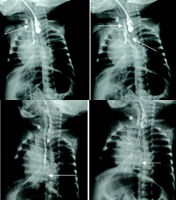

2.X線檢查X線檢查對診斷有決定性意義。方法是取10F較新橡皮導管(管腔內亦可充鋇以利觀察)自口腔或鼻孔插入食管,多於10~12cm處受阻,繼續下插即可見管端返折而出,有時也可捲曲於擴張的近端食管內壓迫氣管而患兒口周發紺、呼吸困難。此刻拔出3~4cm導管後拍胸腹正位或斜位片。導管返折處即為食管近端盲端下緣(橡皮導管彈性而略高於實際水平),用相應的胸椎表示,如果導管返折處位於胸4上緣或胸3下緣,則常為LaddⅢb型,表示食管兩盲端距離小於2cm,一期吻合機會大。X線片中胃和腸管充氣常為Ⅲ型,胃腸不充氣則幾乎全為I型,因有約1%的Ⅲ型因瘺管細小被粘液堵塞,胃腸不充氣,X線表現酷似I型,但其近端食管盲端位置可偏低在胸3水平。由上述可見簡單的插管攝片不但可以診斷食管閉鎖,還可以明確90%以上的型別。導管經氣管食管瘺進入胃內的報告罕見。我們曾見到經瘺管而"吐"綠色液的Ⅲ型病例。Ⅱ、Ⅳ和V型均罕見。診斷較困難。